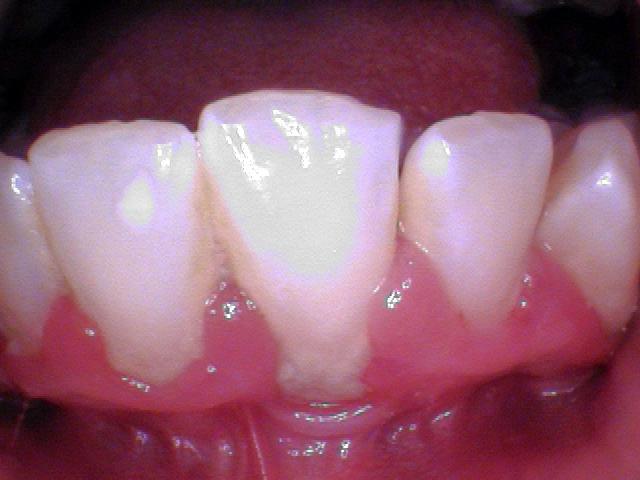

More than half of Americans have some form of gum disease. In the following photos, you can see tartar/plaque on the teeth and inflammation of the gums before periodontal therapy and cleaned tooth surfaces and healthy gums.

In these photos you can see the tenacious calculus on the lower front teeth. This calculus or tarter cannot be removed with brushing and flossing.